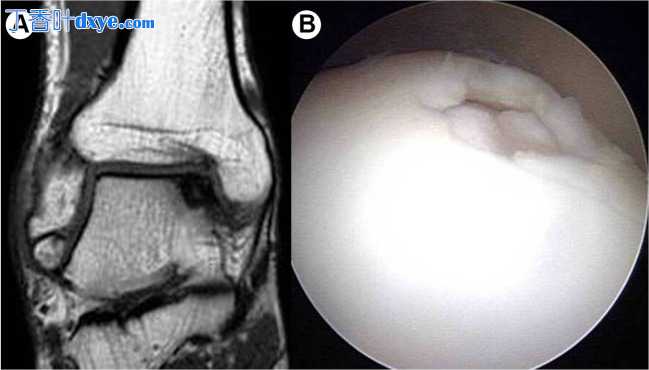

踝关节韧带重建术后 5 个月的患者随访   图1

(A 和 B)继发于重复性外踝扭伤的伴随病理。